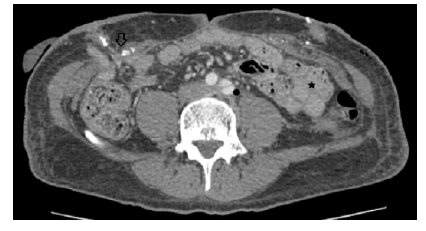

Seat Belt Aorta is often associated with two other injuries collectively referred to as the "Seat Belt Triad", which are abdominal wall disruption and hollow viscus injury (Figure 2). A fourth component, more common in children, is sometimes present, which is a horizontal fracture of the vertebral body, due to flexion-distraction forces acting on the spine, called Chance fracture.2